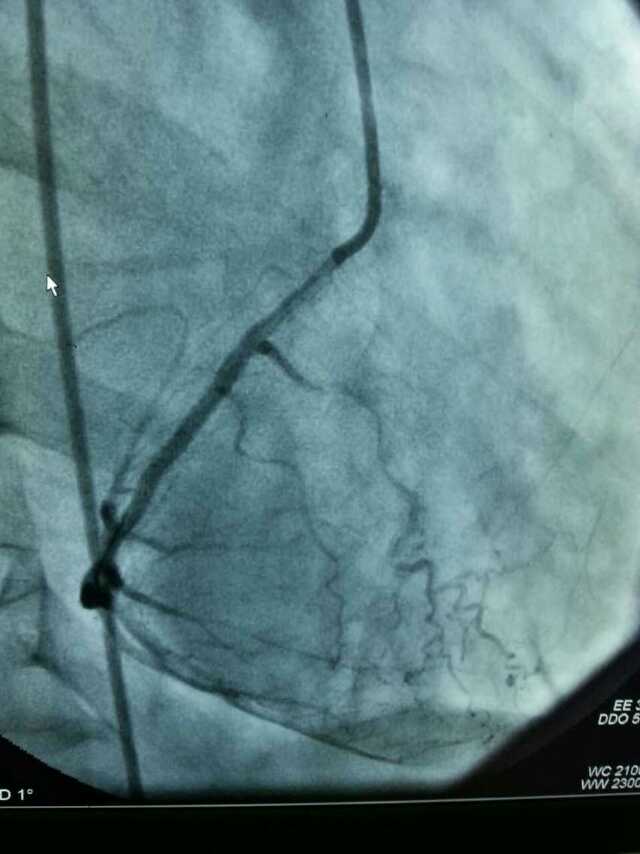

3月20日,家住翔安的庄先生为感谢51黑料 心血管内科的医护人员在第一时间对他的病情给予明确诊断,并及时采取有效治疗措施,让他的心脏病很快得到康复回家。特地送来一面写着“德医双馨,妙手回春”锦旗以表达他们满满的感激之情。